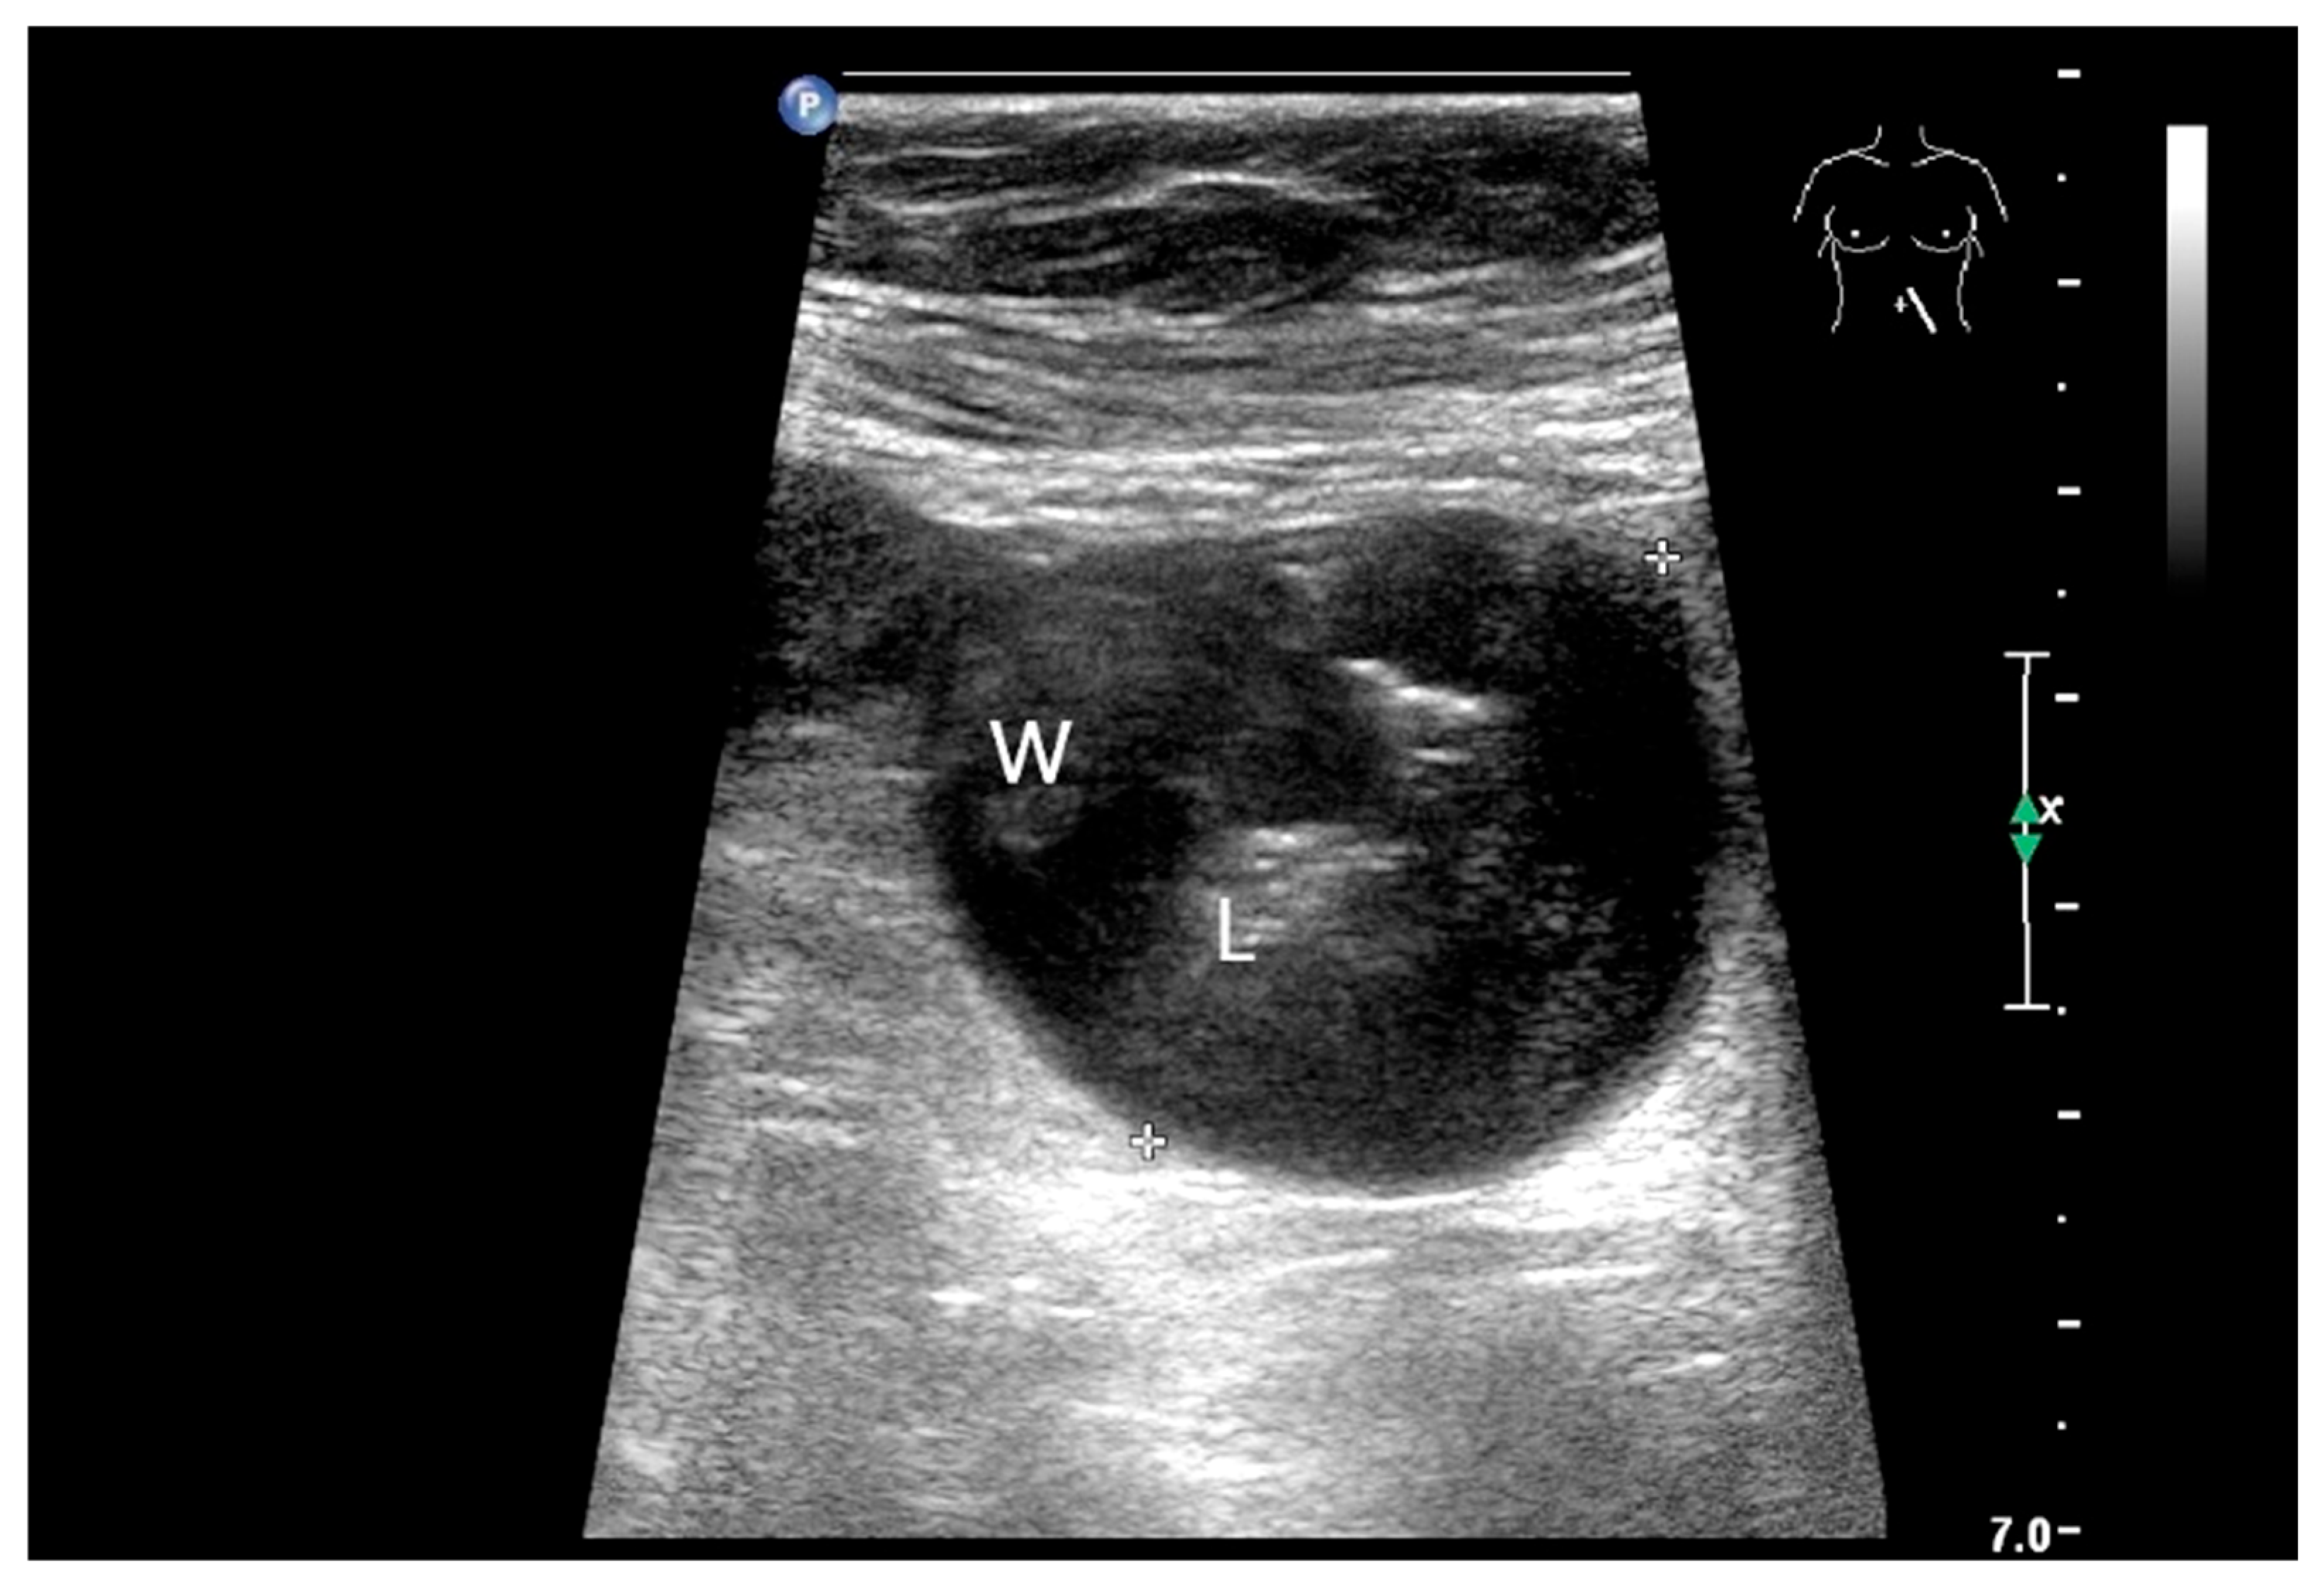

9.1. Gastrointestinal Stromal Tumor

| GIST | Round hypoechoic masses, homogeneous or heterogeneous depending on size. They usually originate from the muscularis propria, which can be difficult to distinguish in US. Small vessels on CDI, hyperenhancement on CEUS. They move with the small intestine and can change position. |

- Bozkurt, T.; Butsch, B.; Schmiegelow, P.; Lux, G. Sonographische Darstellung mesenchymaler Dünndarmtumoren in der Diagnostik von unklaren, gastrointestinalen Blutungen. Ultraschall Med. 1993, 14, 264–268. [Google Scholar] [CrossRef]

- Zhao, L.; Zhao, Z.; Wang, W.; Zhao, W.; Tuo, S.; Shi, Y.; Zhang, W.; Chen, L.; Hong, L.; Yang, J.; et al. Current characteristics on small intestinal stromal tumor-a case control study. Ann. Palliat. Med. 2020, 9, 98–107. [Google Scholar] [CrossRef] [PubMed]

- Zhou, L.; Liao, Y.; Wu, J.; Yang, J.; Zhang, H.; Wang, X.; Sun, S. Small bowel gastrointestinal stromal tumor: A retrospective study of 32 cases at a single center and review of the literature. Ther. Clin. Risk Manag. 2018, 14, 1467–1481. [Google Scholar] [CrossRef]